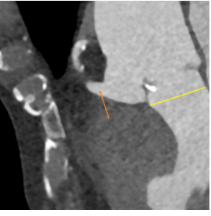

入路:血管情况一般,直径均在7mm以上,但整体均有钙化需要注意;

右侧为主入路,左侧为辅;

升主扩张:平均53mm,最大54.3mm;

三叶瓣:瓣叶无增厚,左右钙化粘连,瓣上可推开空间受限;

左右冠风险较低:术中使用26mm球囊预扩,选用TAV30。

Type1型二叶瓣R-L融合,重度钙化且主要位于瓣叶边缘;瓣叶交界处存在纤维增厚融合,钙化分布局限,在环上3mm-10mm出现。

钙化位置预估人工瓣膜打开形态及植入角度或有影响,存在根部损伤、瓣膜移位及瓣周漏风险,考虑使用球囊预扩,瓣膜选择TAV30。

升主最大直径54.5mm,注意轻柔缓慢。双侧股动脉条件皆可,选择右股为主入路。